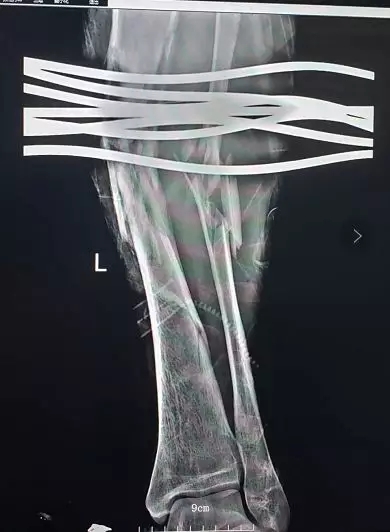

4月18日中午,中山国丹中医院120接到求救称现场有一名小腿被钢筋刺穿的病患,需要马上进行救治。救护人员立刻赶往现场并启用120绿色通道。据患者工友介绍,患者是一名建筑工人,事故由于突发意外状况,导致钢筋不慎插入小腿内。据现场救护人员描述,“当时患者腿上插了7根钢筋,小腿中段就像一个小型马蜂窝现场。

”由于缺少专业拆卸钢筋的工具,导致手术难以进行,现场医生当机立断,立刻拨打119向火炬开发区消防中队寻求帮助。

在现场消防人员的帮助下,医护人员马上为其进行手术。据了解,患者当时钢筋已经穿过小腿腿骨,骨头都已经碎裂,血管与神经都遭到了损毁,情况十分危急。加上术中患者不断的大出血等问题,医生决定马上为其恢复血运,进行了血管、神经的连接,及骨头的固定手术。历经5个小时,手术终于成功完成了。